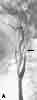

Figure 1

The initial CT scan of the brainshowed a linear hyperdensity in theregion of the left middle cerebral artery,which indicated thrombus formation(Figure 1). An area of cerebral edemawas noted in the region with a smalleffacement from left to right. A cerebralangiogram performed 6 hours after theCT scan revealed a complete dissectionof the left internal carotid artery (ICA)from the second cervical segmentcraniad (Figure 2). A follow-up CTbrain scan 24 hours later demonstrateda large, left middle cerebral arteryischemic infarction with midline shiftingand evidence of left uncal herniation(Figure 3).